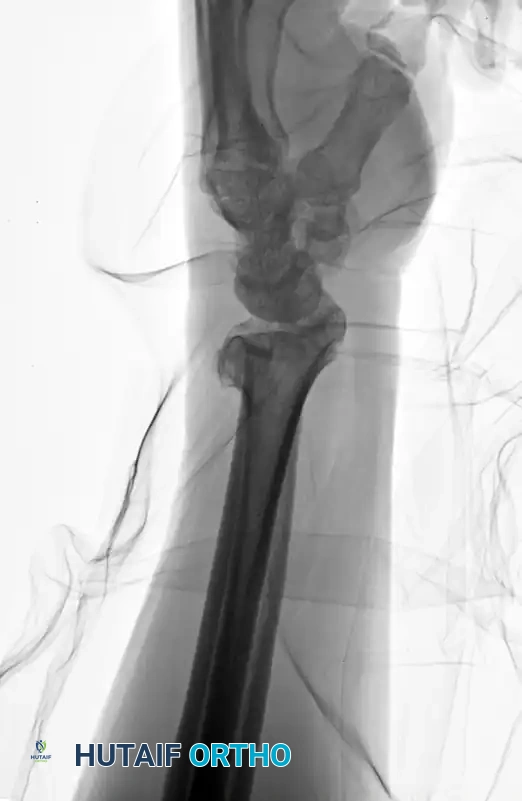

Image

Preoperative Lateral radiograph highlighting severe dorsal comminution and loss of volar tilt.